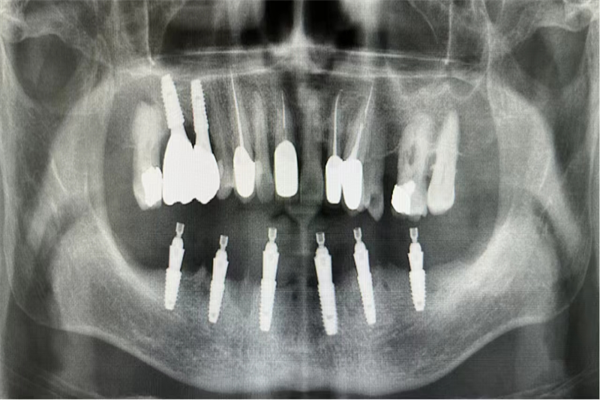

手術(shù)當(dāng)天,楊濤主任和王可醫(yī)生在麻醉科的協(xié)助下,整個拔牙及種植過程十分順利。術(shù)后X線片顯示,種植體的植入深度、角度,高度都非常精準(zhǔn)。

術(shù)后X線檢查,確認(rèn)種植體植入位置

過渡義齒即刻戴牙(告別拔牙后缺牙期)